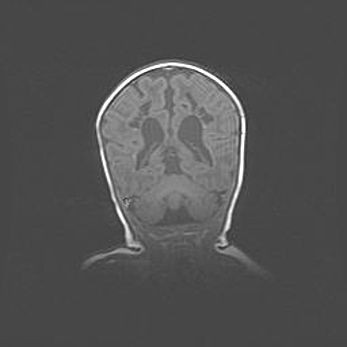

Церебральная ишемия II.

Возраст: 5 дней

Вес: 3400 г

Пол: женский

Окружность головы: 35 см

Срок гестации: 39 недель

Церебральная ишемия – это заболевание, характеризующееся недостаточностью (гипоксией) либо полным прекращением (аноксией) снабжения мозга кислородом по причине закупорки одного или нескольких сосудов. Это приводит к  что метаболическим расстройствам различной степени тяжести в тканях головного мозга, развитию коагуляционных некрозов и гибели нейронов.